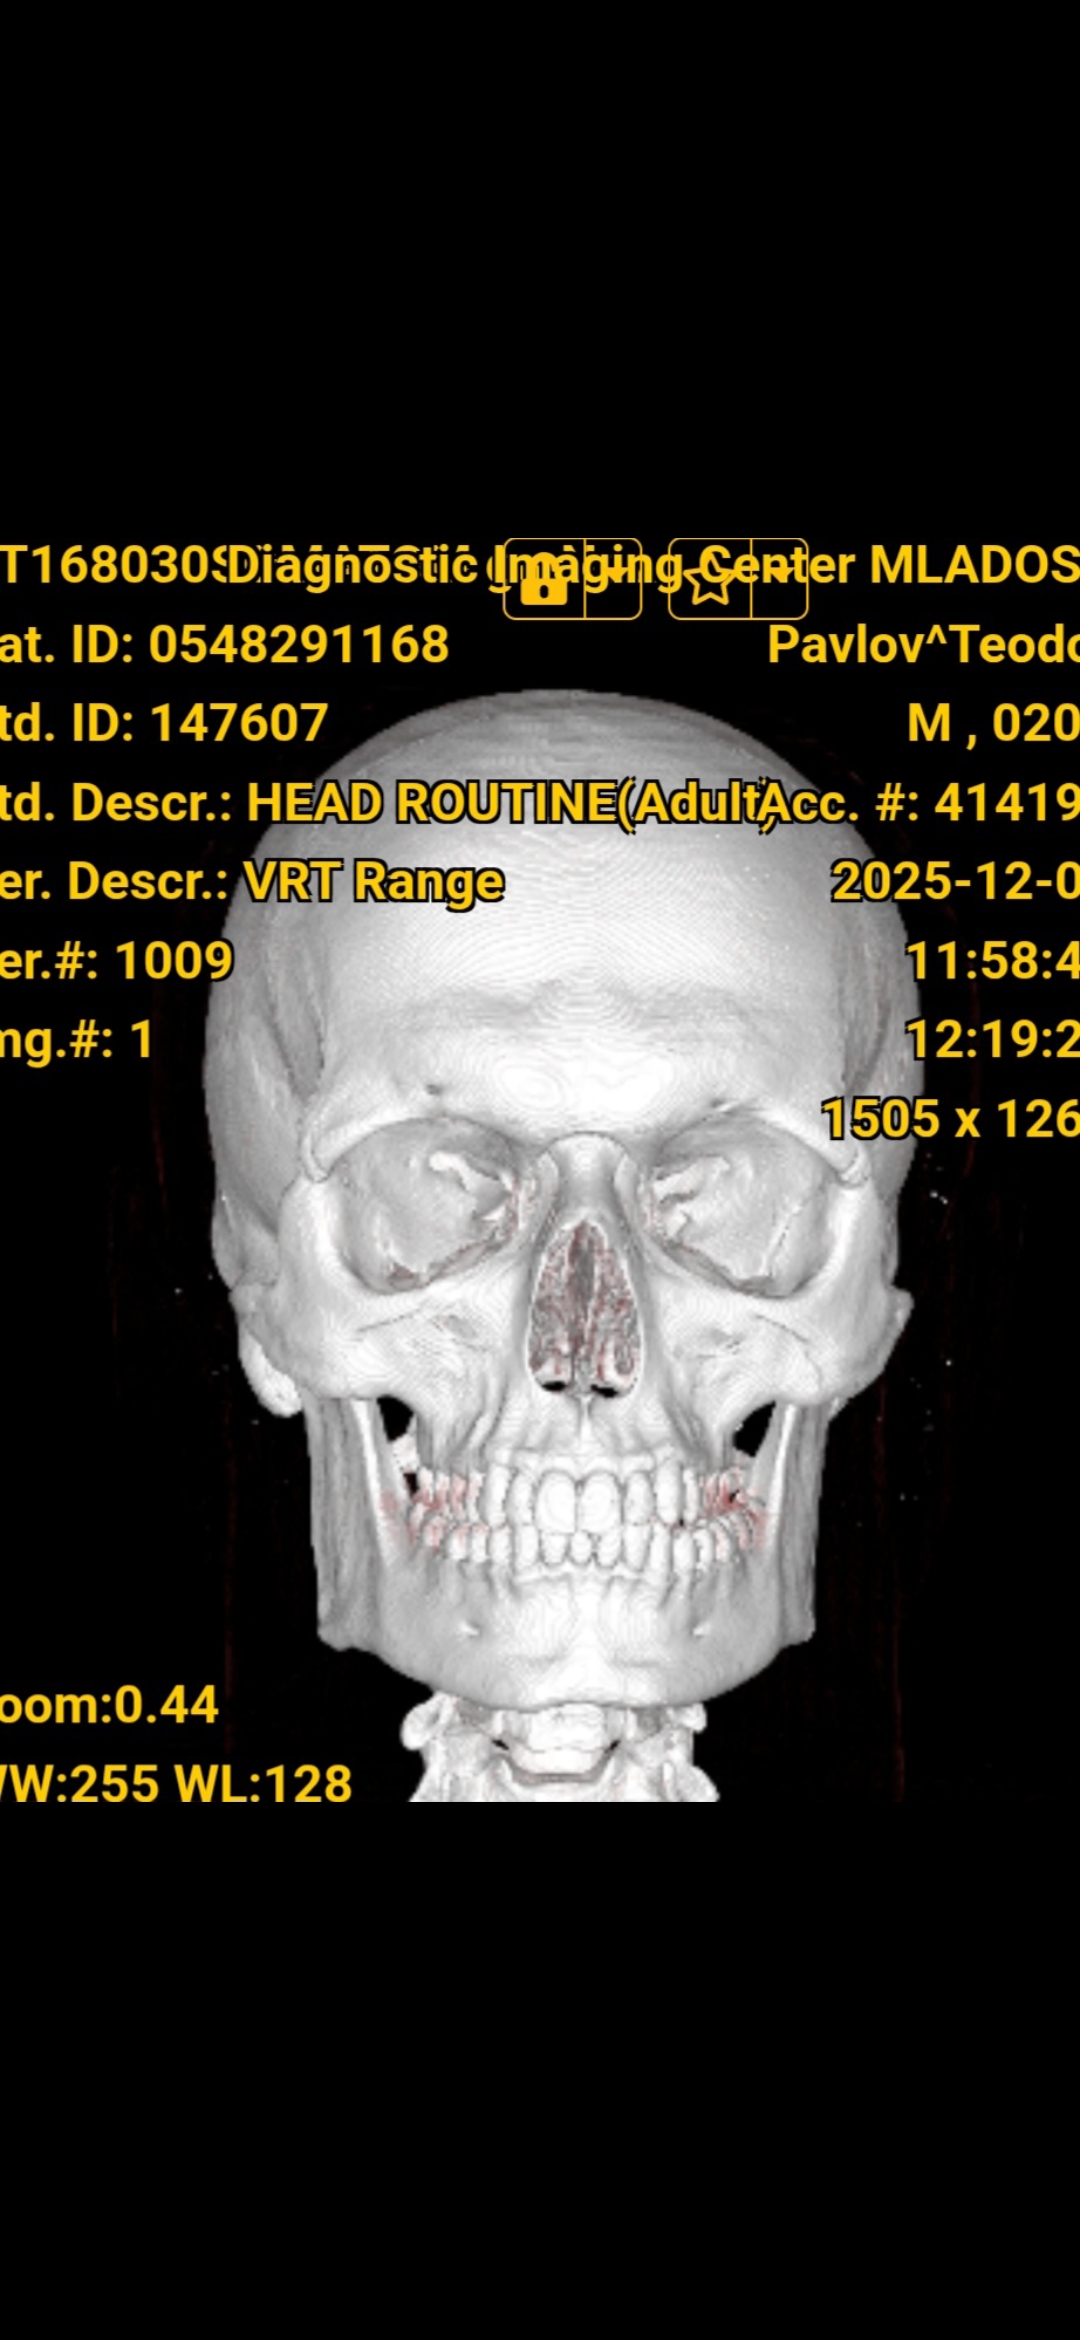

This is my CT Scan:

As you can see my jaw and gonions aren't wide, I measured them with a program and they are about 94mm which is more to the under average side, now the weird thing is, this is how my jaw looks irl

I don't understand how this works and I'm kinda confused

As you can see my jaw and gonions aren't wide, I measured them with a program and they are about 94mm which is more to the under average side, now the weird thing is, this is how my jaw looks irl

I don't understand how this works and I'm kinda confused